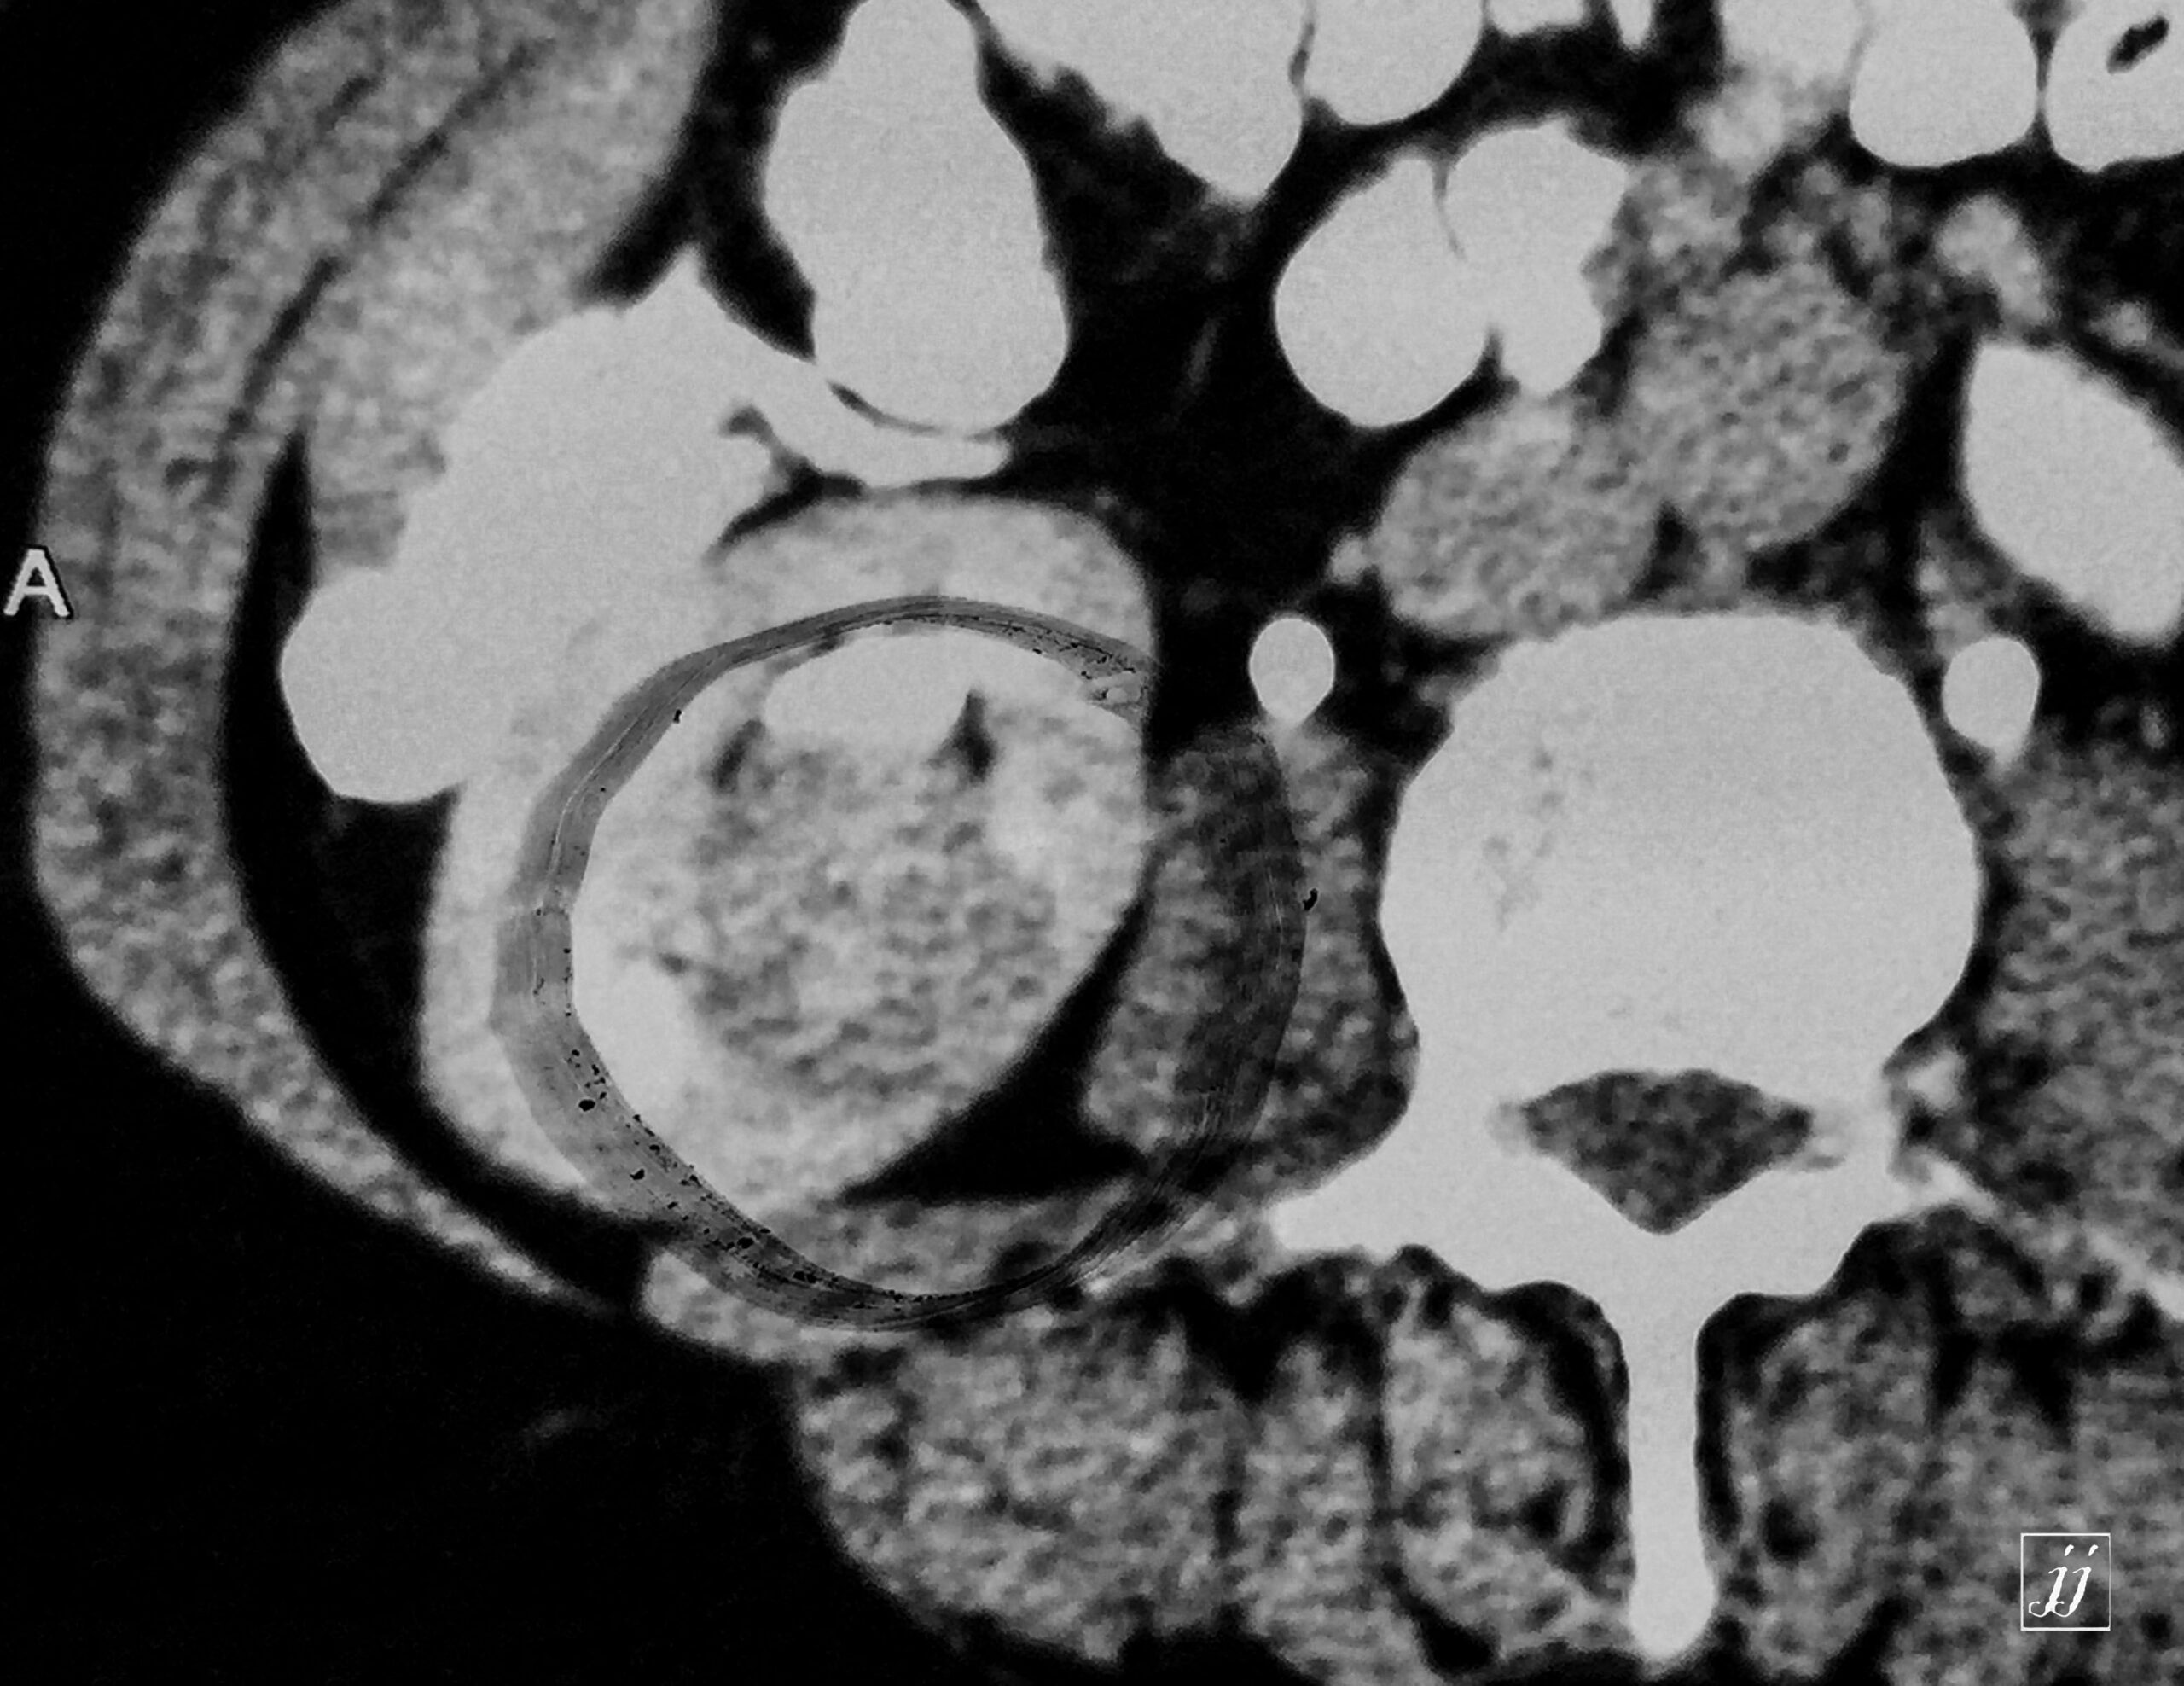

Abdomen- para pelvic right renal tumor (4)